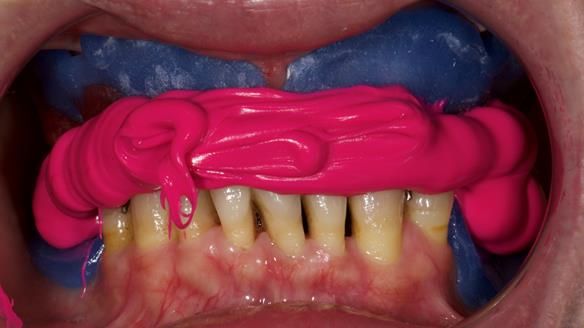

We provided her with an immediate upper denture (Mk 1), followed by a definitive metal-based upper denture (Mk 2). A lower removable partial denture was discussed, to be made only if needed once the upper treatment was complete. However, at review, this wasn’t necessary — Adnana had excellent neuromuscular control and function, even with a shortened dental arch (SDA).

- Immediate denture (Mk 1) fitted the same day the teeth came out

- Definitive denture (Mk 2), metal-based and custom-designed for her face

- A restored smile, restored lip support, and a patient who owned the journey

It’s a clinical story — with practical tips and insight from the surgery and the lab.